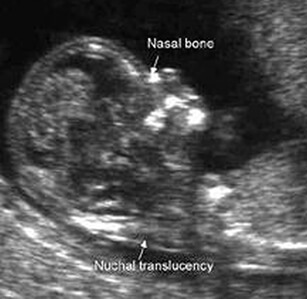

This test is also known as the OSCAR (One-Stop Clinic for Assessment of Risks of Foetal Anomalies). This includes a scan of the nuchal translucency or fluid-filled space behind the foetal neck. A nasal bone assessment is also usually done as babies with Down’s Syndrome may have an absence of the nasal bone. The scans may be combined with a blood test from the mother for hormone and biochemical markers for a more accurate risk assessment.